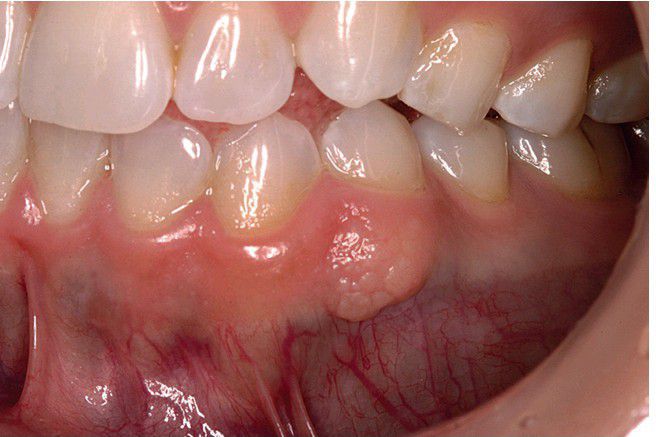

Intramucosal Melanocytic Nevus

. This intramucosal nevus of the mandibular gingiva is nonpigmented. (Courtesy of Dr. James Jacobs.)